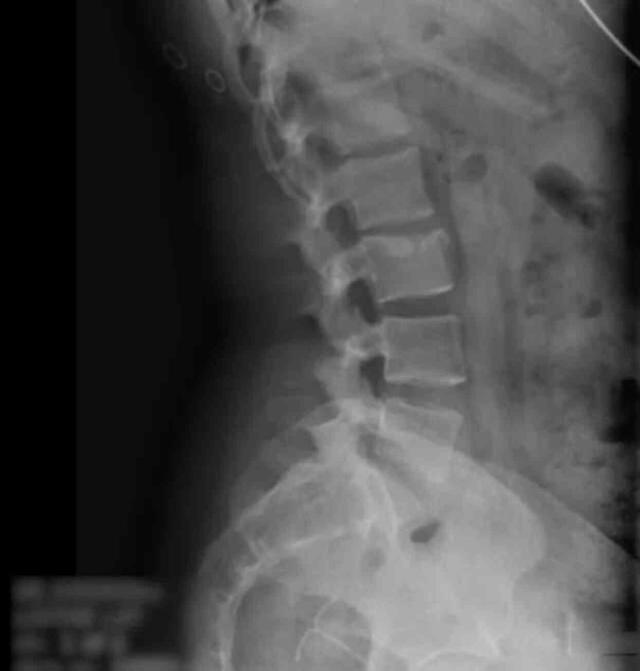

29 yaşındaki Daniella Hampton, 12 yıl önce kullandığı doğum kontrol cihazının rektumunda bulunmasından sonra büyük bir şok yaşadı. 2009 yılında rahmine yerleştirilen bakır spiral adı verilen intrauterin bir cihazı kullanmıştı. Altı hafta sonra düştüğü söylenmişti ve doktorlar cihazın varlığını teyit edememişti. Daniella, cihazın hâlâ vücudunda olduğuna inandı ve yıllarca ağrı çekti. Bir araba kazasında çekilen röntgen sonucunda cihazın rahmini delerek kalın bağırsağına yerleştiği anlaşıldı.

İki çocuk annesi Daniella, yıllarca kısırlık tedavisi görmesine rağmen, aslında içinde bir doğum kontrol cihazı olduğunu bilmiyordu. Bir araba kazasında sonra çekilen röntgen sonucunda cihazın rahmini delerek kalın bağırsağına yerleştiği anlaşıldı.